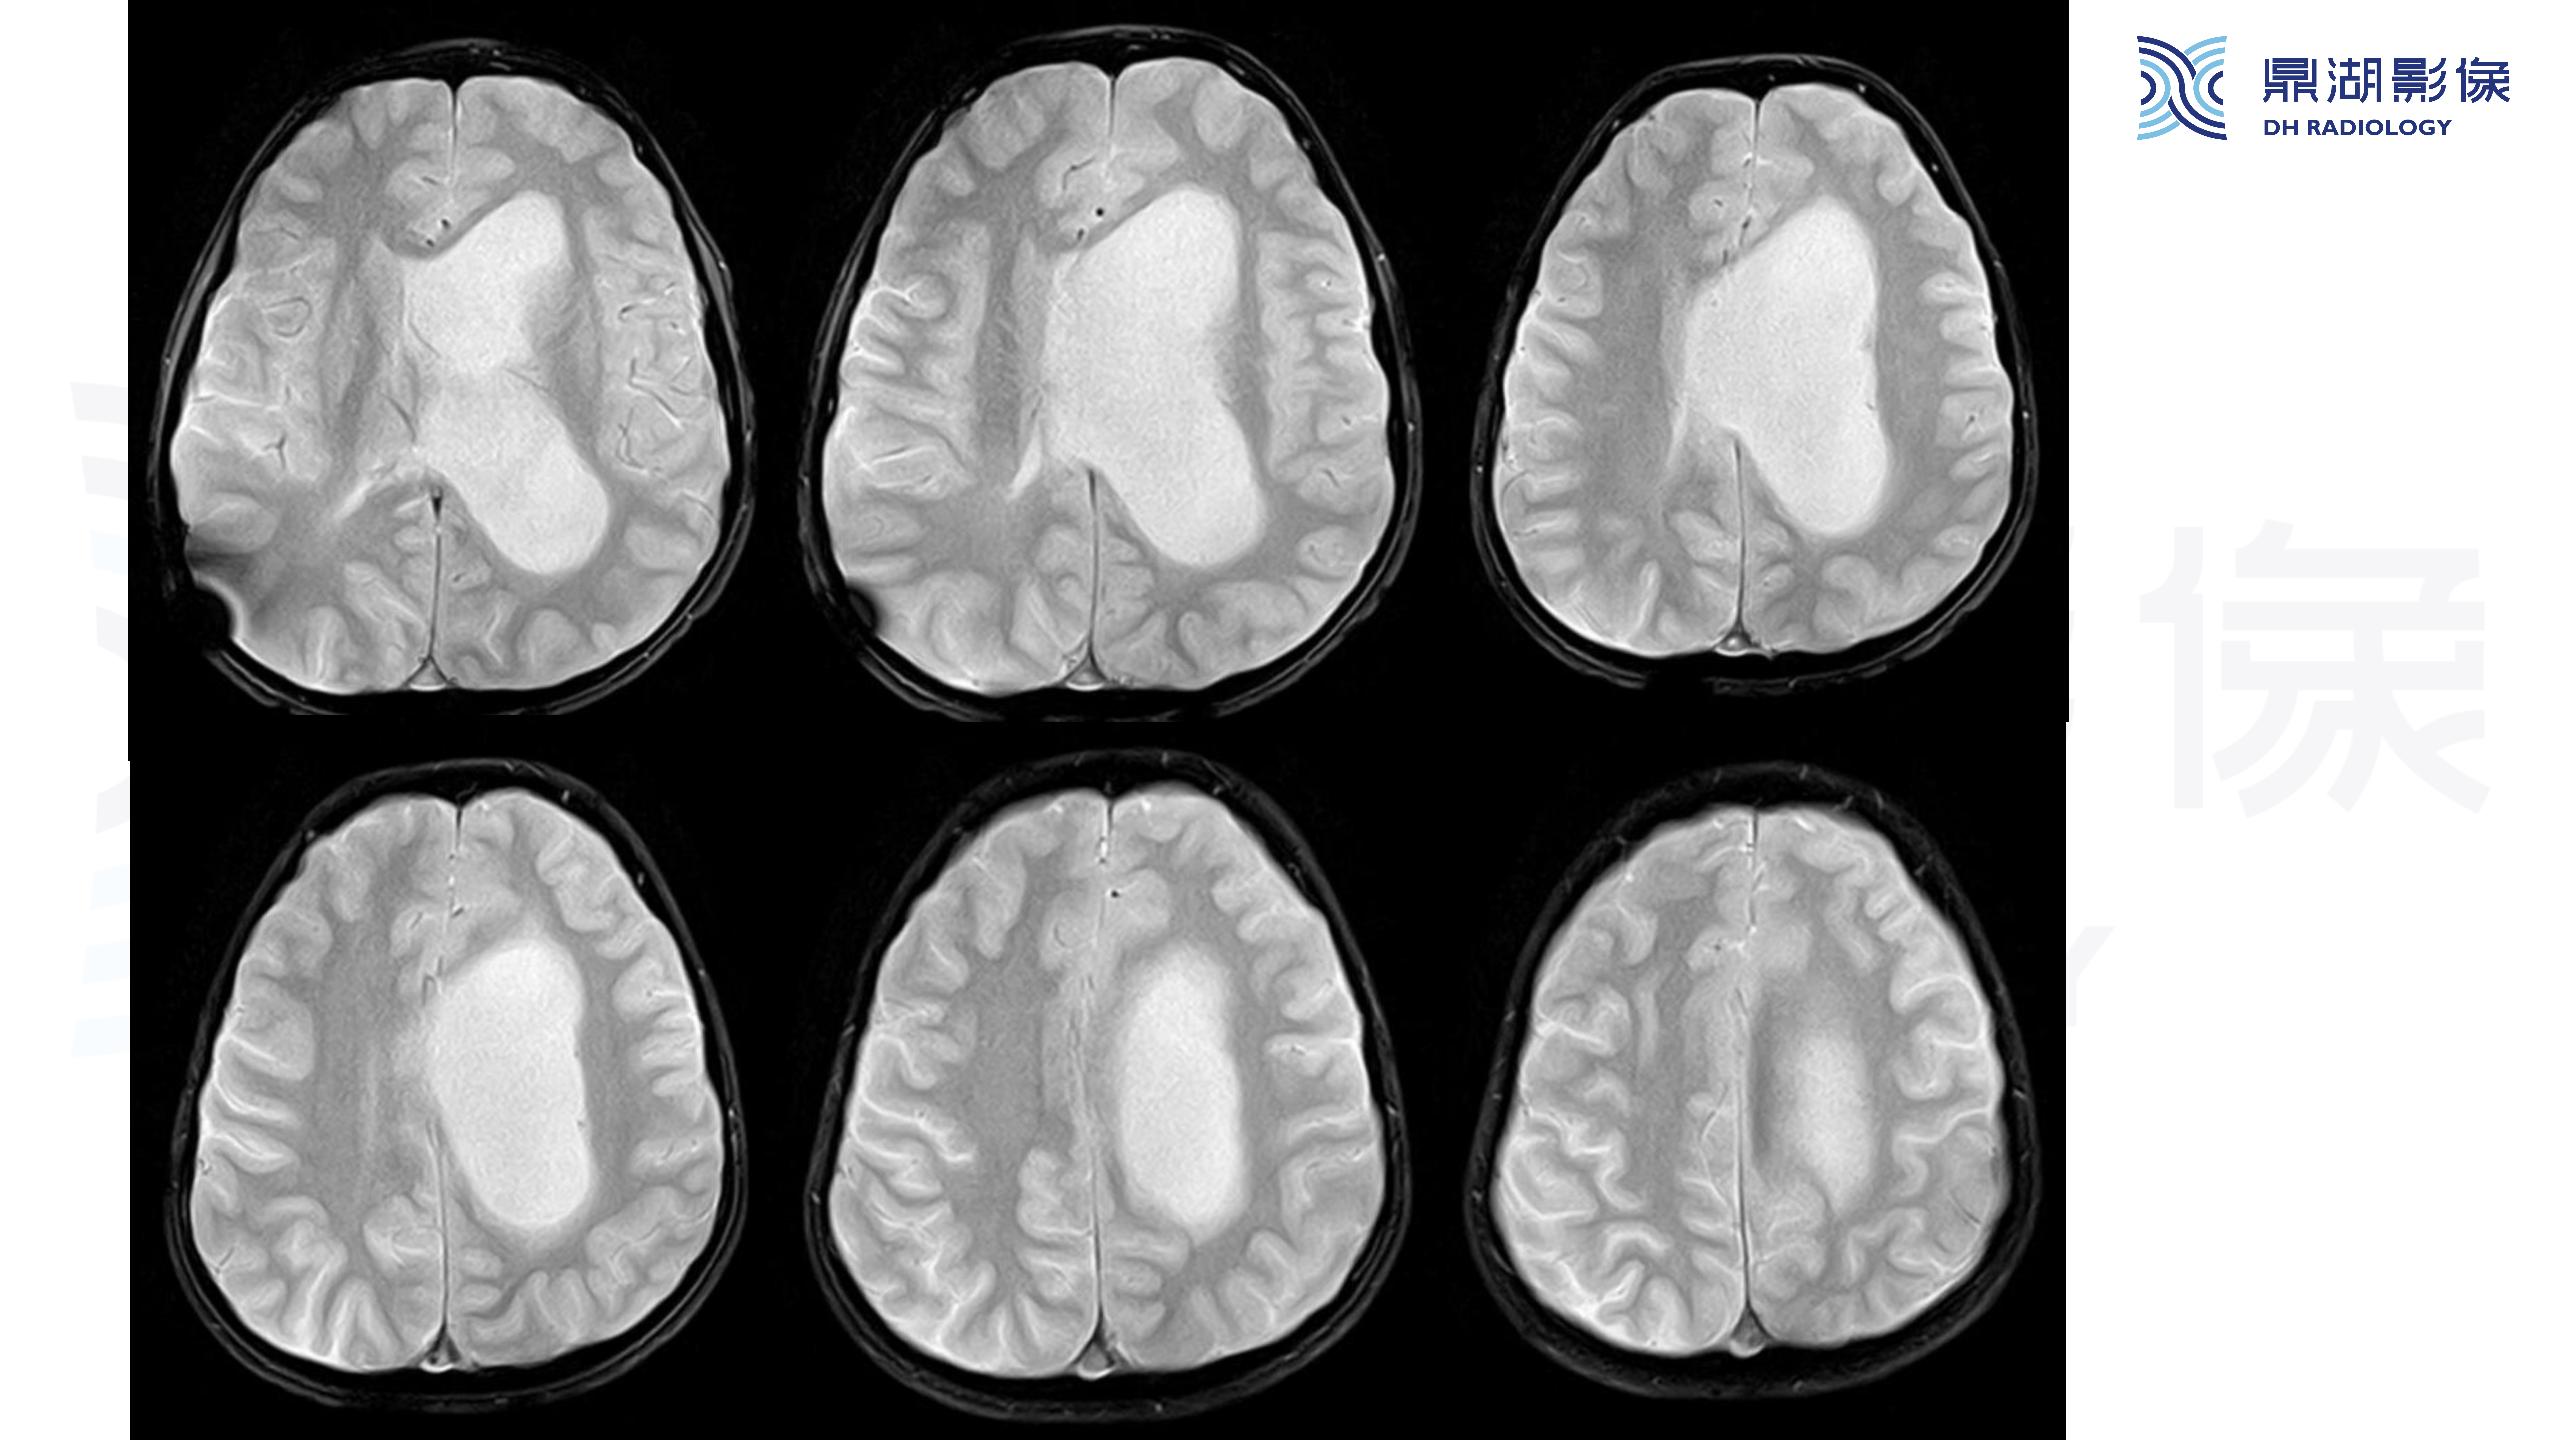

裂隙脑室综合征 (slit ventricle syndrome,SVS)-鼎湖社群读片病例